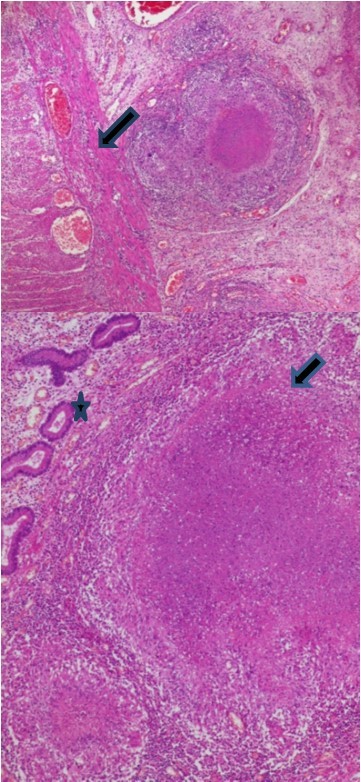

The histopathologic examination of the resected bowel specimen showedcaseating granulomatous inflammation (Figure 2), consistent with intestinal small bowel tuberculosis complicated with peritonitis and perforation (Figure 3).

Figure 2.Epithelioid granuloma and giant cells (Arrow) with caseous necrosis (Star)